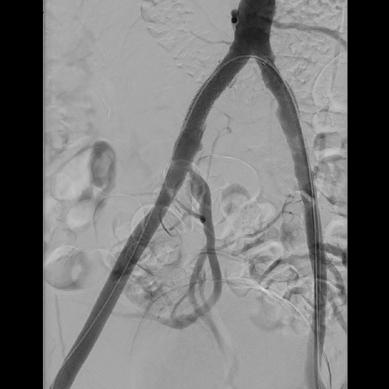

TAME was performed via an ipsilateral antegrade femoral approach and patients were evaluated for all target branches of the posterior tibial artery and peroneal artery.

Using the Numerical Rating Scale (NRS) to assess pain, Yuan shared that 67 out of 82 patients achieved a ≥50% improvement om symptoms at 12 months post procedure. The mean baseline Victorian Institute of Sports Assessment Achilles (VISA-A) score was 48.4±19.1, which improved to

76.9±17.4 and 82.2±17 at six and 24 months, respectively.

In subgroup analyses carried out by Yuan et al, superior success rates were noted among recreational athletes (87.5%) following TAME compared to competitive athletes (61%). When stratified by technique, Yuan et al found that super-selective embolization had a success rate of 84.5%, compared to 63.6% for embolization from the main trunk. Regarding the superior success rates in recreational athletes, Yuan explained that: “Those that compete at a high level seek to go back to training as soon as possible, while the recreational athletes have the privilege of rest after their treatment. These findings support TAME as a viable option that offers these patients a potential pathway to recovery and restored activity levels,” said Yuan.